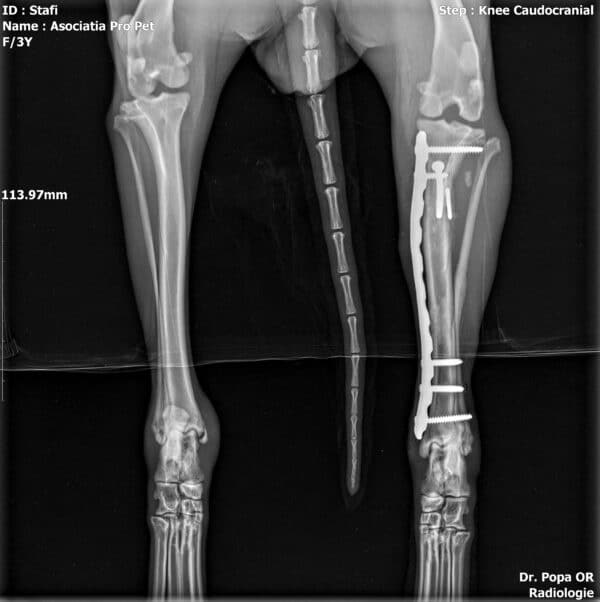

Jubina im Vet-House ist operiert, total menschenbezogen und verschmust und sehr sehr dünn. Wenn sie da raus muss, hat sie sicher wenig Chancen..

Röntgenbilder nach OP zugefügt.

JUBINA wurde angefahren und hat einen gebrochenen Hinterlauf, der zeitnah operiert wird (10/2022).

Beinbruch nach Autounfall, wurde operiert, aktuell viel zu dünn (10/22)